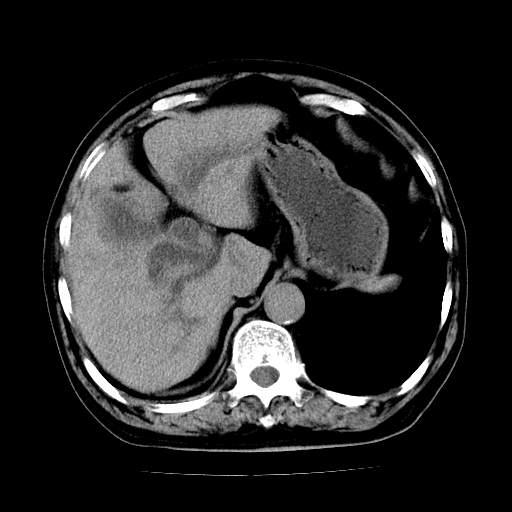

标题: CT25226:男,71岁,皮肤黄染四天。 [打印本页]

男,71岁,皮肤黄染四天。

肝内外胆管及胆总管上段扩张,考虑为梗阻所致,建议mrcp检查。

考虑胆总管癌并肝内外胆管扩张。

支持考虑胆总管癌并肝内外胆管扩张。 局部应薄扫。心包钙化。

胰腺上端胆总管内见软组织影,强化不明显,结合临床,还是考虑低位梗阻性黄疸,胆总管癌可能性大